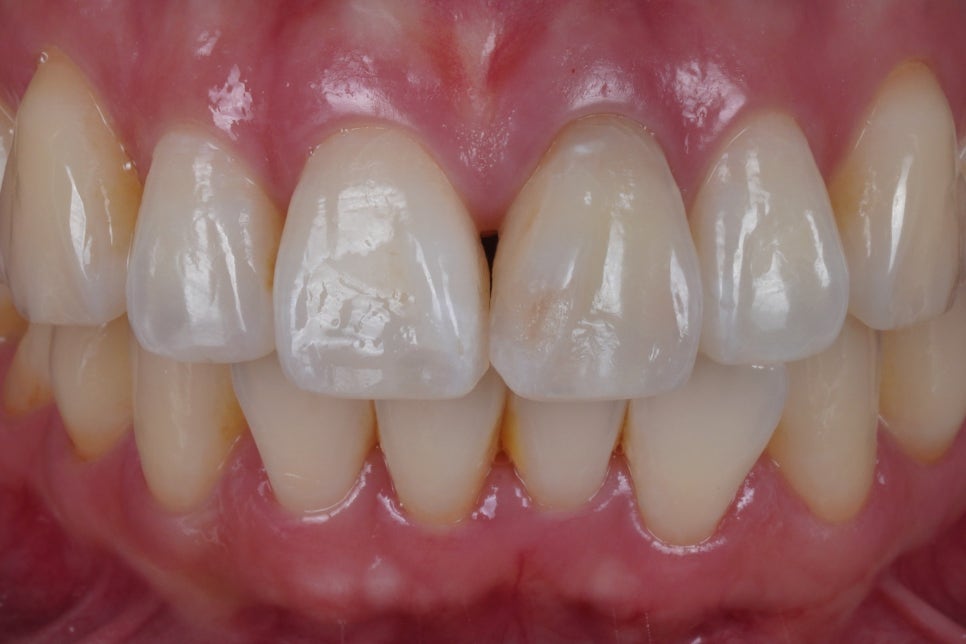

완전히 색상이 다 돌아왔다고 판단이 되면

뚫어놓은 구멍을 단단하면서도

치아와 접착이 잘 되는

레진으로 메꾸게 됩니다.

저는 이 상태에서

굳이 크라운을 할 필요가 없다고 생각해요.

특히 젊은 분들인 경우에요.

크라운을 함으로 인해서

잃게되는 치아 부피가

너무나도 크다고 생각하기 때문입니다.

앞서 말씀드렸듯이,

저희는 보존적인 치료를 주로 하는 곳이니까요.

출처 아카이브 열기앞니 하나만 변색되어

실활치 미백을 고민하고 계시다면

라미네이트, 또는 크라운 치료 대신

치아를 최소한으로만 삭제하는

실활치 미백 + 레진 코어 마무리 방법을

먼저 생각해보셨으면 좋겠습니다.